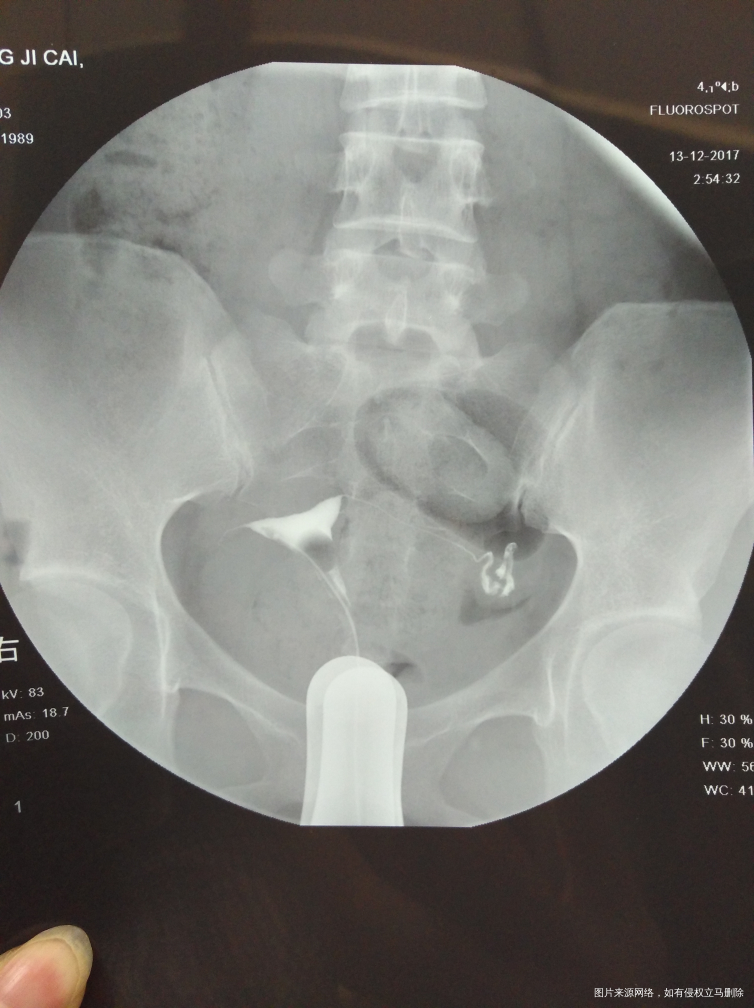

麻烦医生指点,输卵管通而不畅要怎么治疗?我的右侧输卵管部分切除,所有希望都寄托在这跟管上了,我不想试管,想自然怀孕,帮帮忙指点

,谢谢!从哪里看的出通而不畅的,也帮忙指点一下

您好,你这种情况考虑试管婴儿比较合适您,从图上看还有盆腔炎,如果你不想试管坚持自己试可以考虑手术,术后自然妊娠几率低,请慎重考虑

你好,从您的片子看,盆腔弥散局限,所以输卵管通而不畅。可以选择中药治疗。最多半年,如果不怀,可以选择手术或者试管。祝您早日好孕。如果满意我的回复,记得采纳。

你好,从您的片子看,盆腔弥散局限,所以输卵管通而不畅。可以选择中药治疗。最多半年,如果不怀,可以选择手术或者试管。祝您早日好孕。